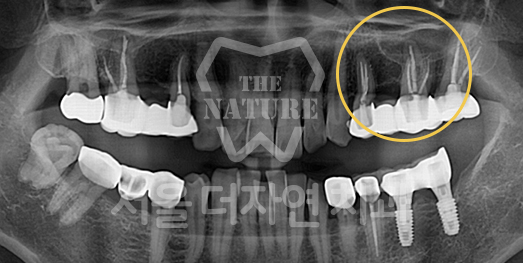

전체 임플란트는 위턱과 아래턱의 교합, 잇몸뼈의 상태 및

얼굴 변화 등 모든 것을 고려해 식립해야 합니다.

서울더자연치과는 3D 디지털 기술의 정밀 진단을 바탕으로

수술 계획을 세워 수술을 집도합니다.

잇몸뼈가 얇은 상태

잇몸뼈 충분히 이식 후 임플란트 식립

성공을 위한 노하우, 잇몸뼈 재건 기술

전체 임플란트를 해야하는 환자들은

대부분 고령의 환자들로 오랜 틀니 사용

또는 노화로 인해 치조골이

거의 남아있지 않는 경우가 많습니다.

이 때, 치조골 이식을 병행하여 잇몸뼈 재건 후 안정적인 임플란트 식립을 하고 있습니다.

치료기간 : 2021.04.12~2021.09.15